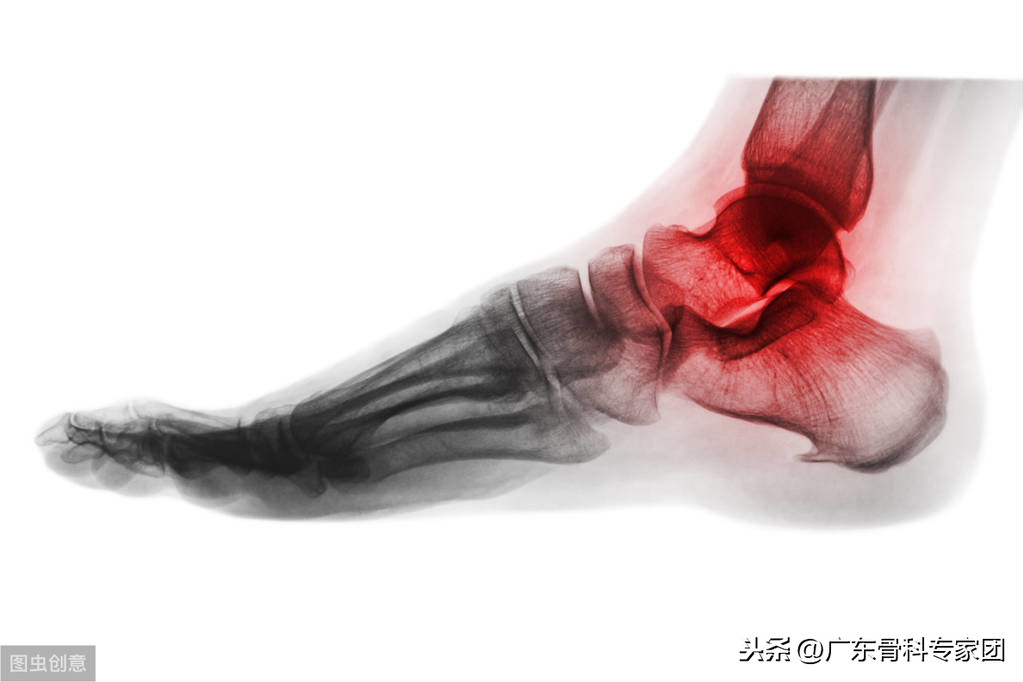

足跟痛又称为跟痛症,是由一系列病因引起的足踝部症候群。而与足跟紧密相连的步行活动会受到相应不同程度的影响,有碍正常的日常活动。为了缓解足跟疼痛,病因的确定不可少之。那么一般引起足跟痛的原因有哪些?该如何处理?

足跟痛是指足跟一侧或两侧疼痛,通常不伴有红肿。引发足跟痛的病因主要有以下几个: